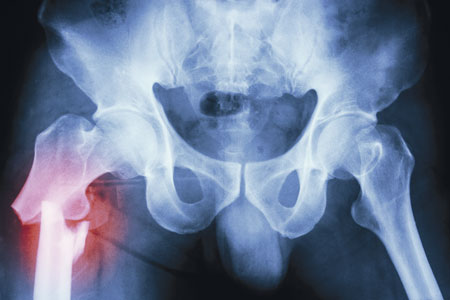

Det är omdiskuterat hur länge bisfosfonatbehandling av osteoporos bör pågå, vilket främst beror på sällsynta biverkningar. Foto: Colourbox

Bisfosfonater rekommenderas av Socialstyrelsen som förstahandsbehandling vid osteoporos och hög frakturrisk tack vare stor effekt, låg kostnad och hög evidens. Det är omdiskuterat hur länge bisfosfonatbehandling av osteoporos bör pågå, vilket främst beror på sällsynta biverkningar i form av atypiska femurfrakturer.